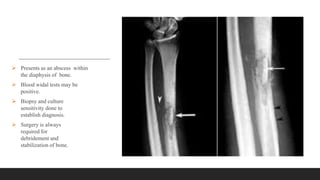

 Presents as an abscess within

the diaphysis of bone.

 Blood widal tests may be

positive.

 Biopsy and culture

sensitivity done to

establish diagnosis.

 Surgery is always

required for

debridement and

stabilization of bone.